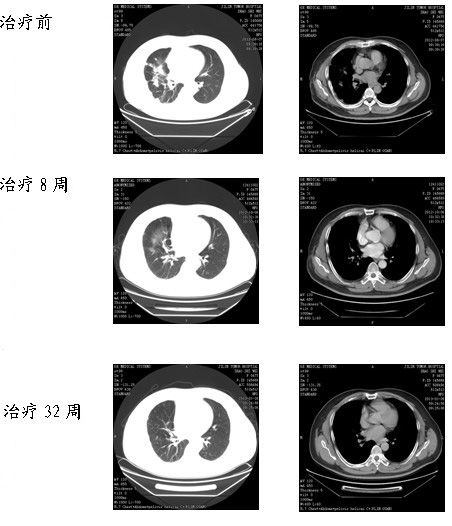

臨床診斷:右肺下葉背段及中葉中分化腺癌楔形切除術(shù)后(cT4N2M1b)Ⅳ期,右胸壁轉(zhuǎn)移活檢術(shù)后、右肺內(nèi)轉(zhuǎn)移、縱隔淋巴結(jié)轉(zhuǎn)移、右側(cè)胸膜轉(zhuǎn)移?;颊叻螪ACOMITINIB(達克替尼)與厄洛替尼對照2、3線治療晚期非小細胞肺癌的臨床研究的入組標準,經(jīng)與患者及家屬詳細溝通,告知參加臨床研究可能獲益及可能承擔風險,患者及家屬表示知情,同意參加臨床實驗,簽署知情同意書,入組臨床試驗,現(xiàn)口服厄洛替尼/安慰劑和PF-00299804/安慰劑每天各一片,8周后復查CT療效PR,現(xiàn)已口服藥物,32周,療效CR。